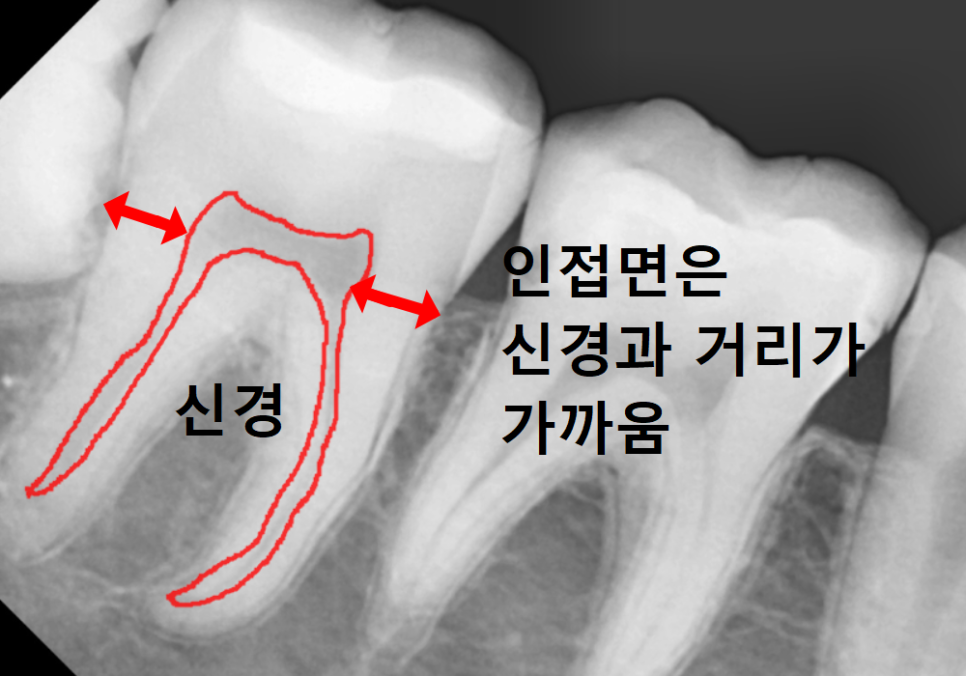

하지만 엑스레이를 찍어보니

상황이 조금 달랐습니다.

사랑니가 앞 치아(#47) 쪽으로

비스듬히 누워 있는 상태였거든요.

221231

엑스레이를 찍어도

사랑니에 가려져 있으면

충치 크기를 정확히 가늠하기 힘들죠.

둘째, 진행 속도가 압도적으로 빠릅니다.

치아의 겉면인 '법랑질'은 씹는 면에 비해

옆면이 훨씬 얇습니다.

그래서 일단 충치가 시작되면

금방 내부의 '상아질'을 타고

신경까지 도달해 버립니다.